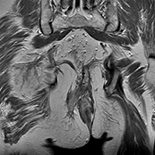

Perianal fistulas are malformations of the anorectal area. Accurate preoperative assessment of perianal fistula tract is a main assumption in diagnosis of the disease, affecting the operation efficiency. The aim of the study was to present our experience in application of a new diagnostic protocol based on the magnetic resonance imaging (MRI) examination using a mixture of hydrogen peroxide (HP) and gadolinium as a direct contrast medium in evaluation of recurrent fistulas tract. The method is referred to as HPMRI.

The study group consisted of 12 subjects operated on from 2011. Direct HPMRI fistulography was performed in all subjects before the operation. All types of fistulas were precisely evaluated by HPMRI examination.

Intraoperative state confirmed complete course of fistulas in 11 cases. In 1 case, an internal opening was not found.

We suggest that this new method of direct HPMRI fistulography may improve visualization of the tracts of recurrent fistulas and improve efficacy of surgical procedures.